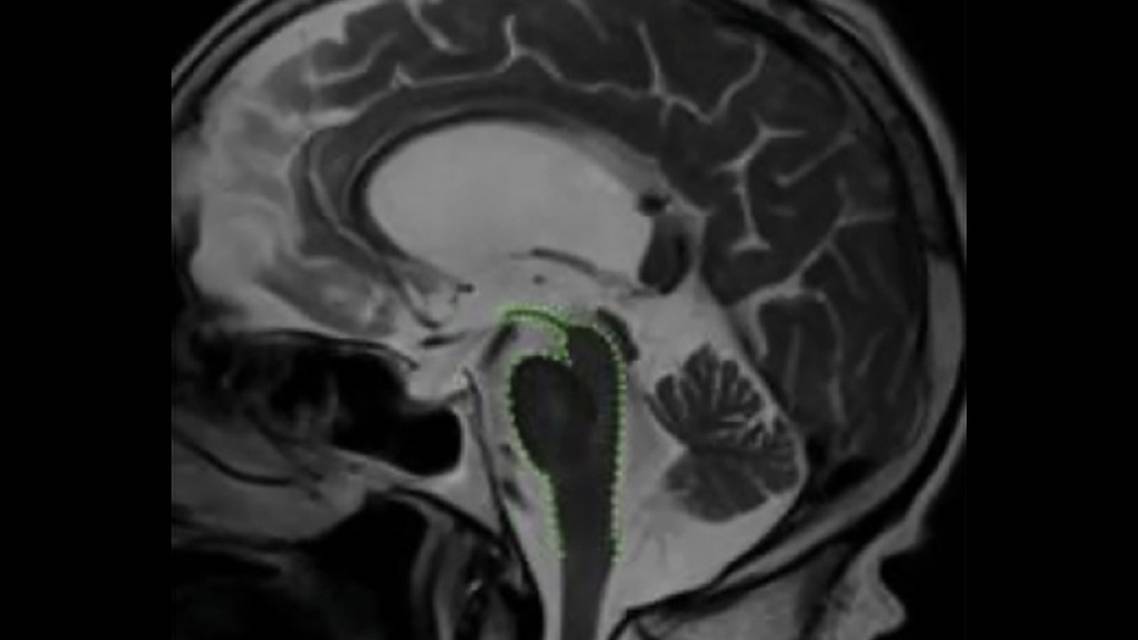

Structural neuroimaging with CT or MRI in people with PSP show generalized and brainstem atrophy, particularly involving the midbrain. Midbrain atrophy with relative preservation of the pons results in the radiologic “hummingbird sign” on midsagittal view (Figure 1) or the “morning glory sign” on axial brain MRI or CT.2 Fluorodeoxyglucose-positron emission tomography (FDG PET) may demonstrate decreased glucose metabolism in the midbrain.9 Certain morphometric indices, including reduced midbrain to pons midsagittal surface ratio, can help support the diagnosis of PSP with variable sensitivities and specificities.10 Increased diffusivity values in the putamen, caudate nucleus, and globus pallidus have been found on apparent diffusion coefficient (ADC) and diffusion-weighted imaging (DWI) brain MRI in people with PSP. Iron deposition patterns in different parts of the basal ganglia, including putamen, caudate, and globus pallidus, on susceptibility-weighted imaging (SWI) have also been found in persons with PSP. Resting-state functional MRI (fMRI) studies in PSP have also shown disruptions in the connection between the dorsal midbrain and cortical/subcortical networks.10